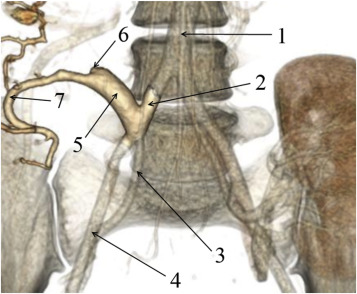

In one case, anastomotic dehiscence of the interduodenal anastomosis had caused the duodenal leakage with parapancreatic fluid collection formation in a female patient (Patient 25; Figure 2).

Gastrointestinal tract contrast X-ray radiography; (1) nasal-intestinal probe is ...

Gastrointestinal tract contrast X-ray radiography; (1) nasal-intestinal probe is inserted beyond the ligament of Treitz; (2) contrast-filled small-bowel loops; (3) contrast traveled into the drain through the interduodenal anastomosis dehiscence; (4) drain is inserted close to the vicinity of the interduodenal anastomosis; (5) visualized lines of staples sutures of the donor duodenum.

Transcutaneous drainage of the duodenal leak was performed under ultrasound and x-ray guidance. Prolonged drainage of the concerned area yielded a positive outcome. During fistulography, sufficient closing of the duodenal fenestration was confirmed. Following the fistulography, closure of the drainage canal was completed by using a blend of Type 1 human collagen with cancellous bone chips.